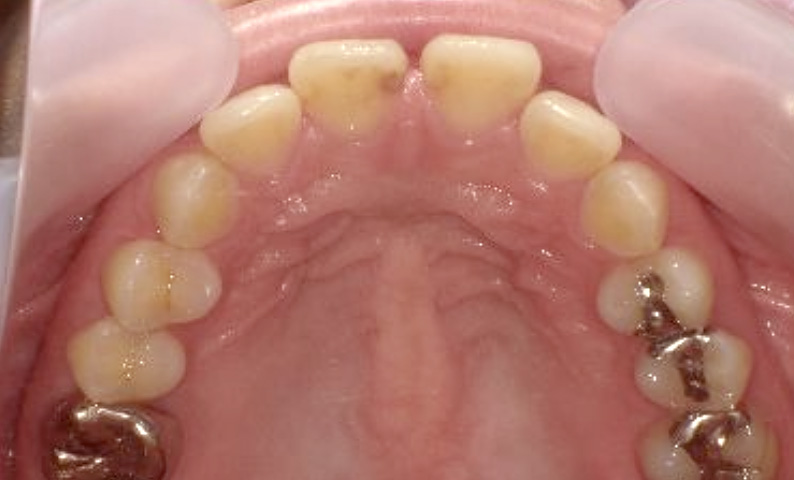

症例_022 上顎だけの部分矯正

治療期間:9ヶ月金額:30万円+税女性前歯のガタガタ前歯のガタガタ上の前歯だけ

| Before | After |

|---|---|

|